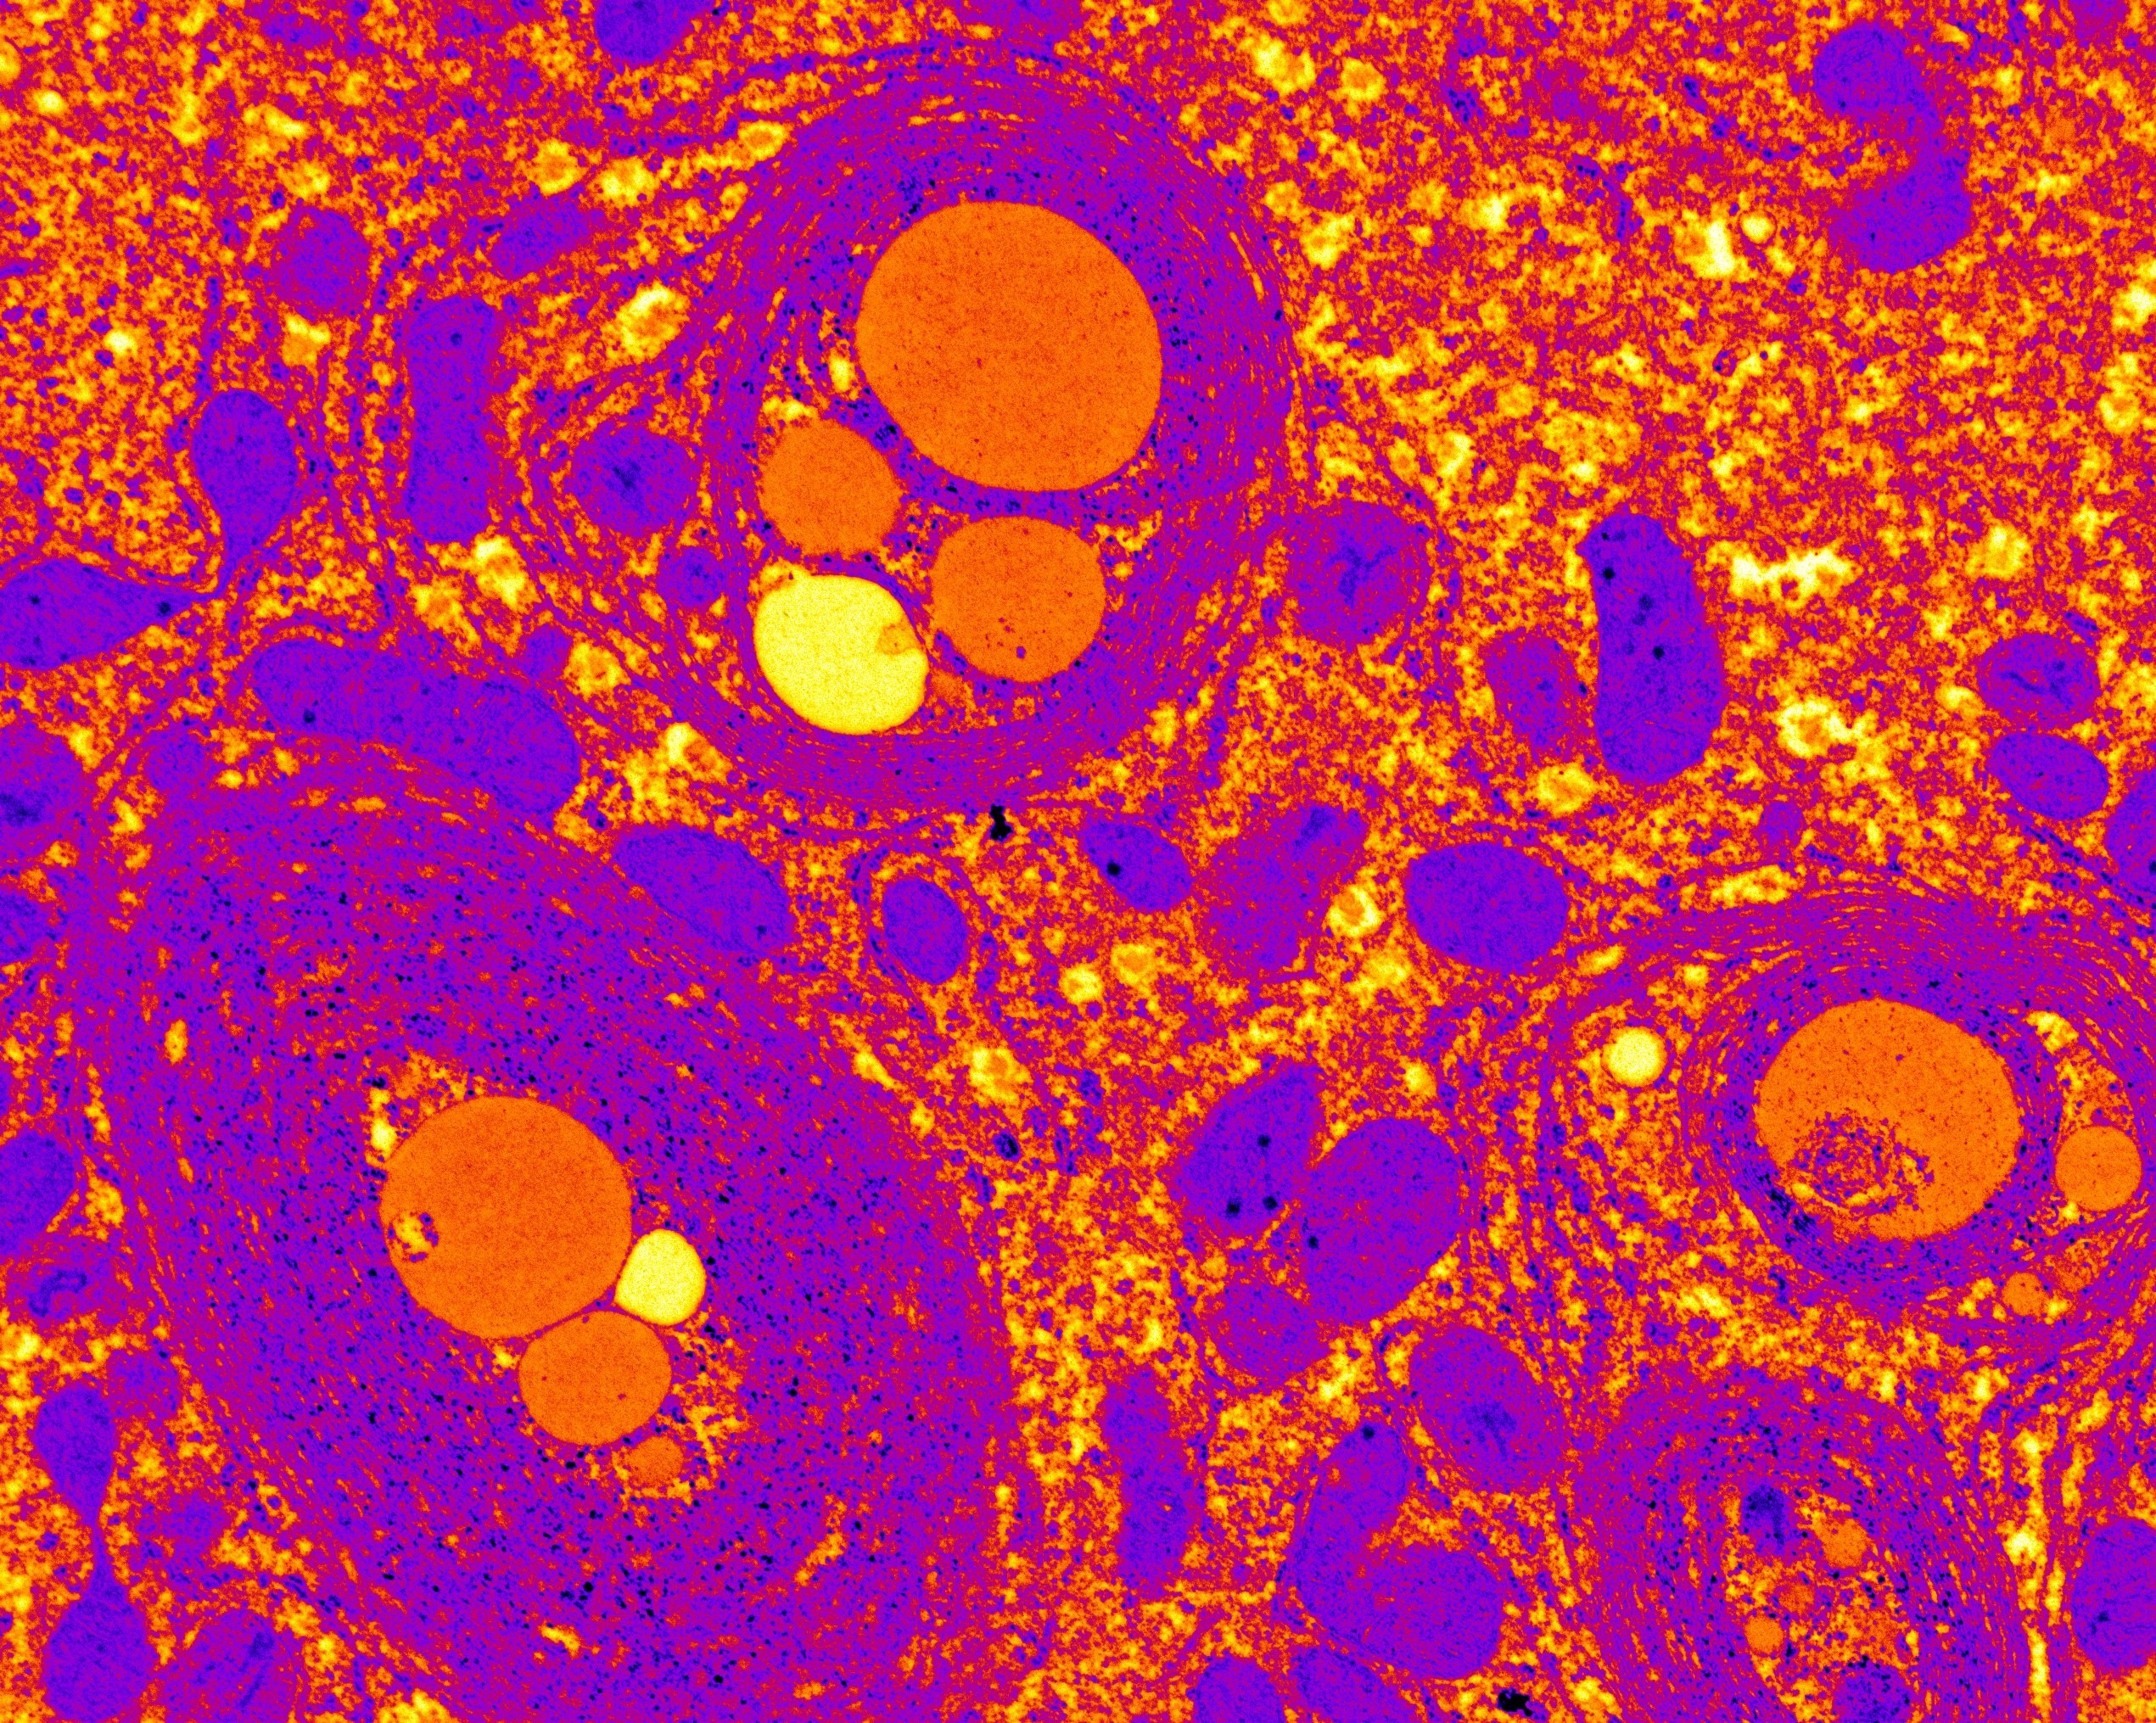

Logran aliviar la neuropatía diabética a través de la administración de monóxido de carbono